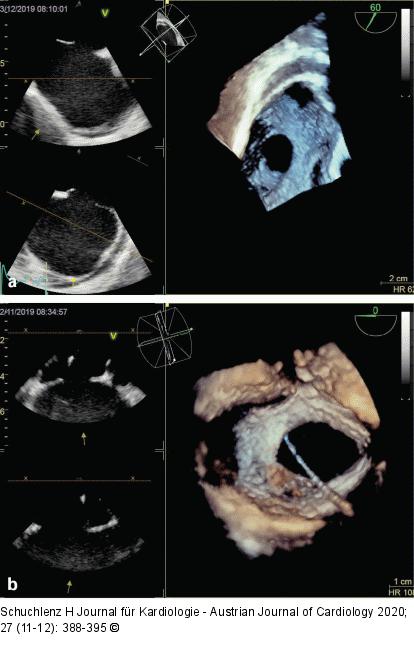

Abbildung 6: ASD II (a): Transösophageale 2D-Echokardiographie (links) und 3D (rechts) eines ASD II, Aufsicht von rechts; (b): Transösophageale 2D-Echokardiographie (links) und 3D (rechts) eines ASD II, Aufsicht von rechts mit Sondierungskatheter. |

(a): Transösophageale 2D-Echokardiographie (links) und 3D (rechts) eines ASD II, Aufsicht von rechts; (b): Transösophageale 2D-Echokardiographie (links) und 3D (rechts) eines ASD II, Aufsicht von rechts mit Sondierungskatheter. |